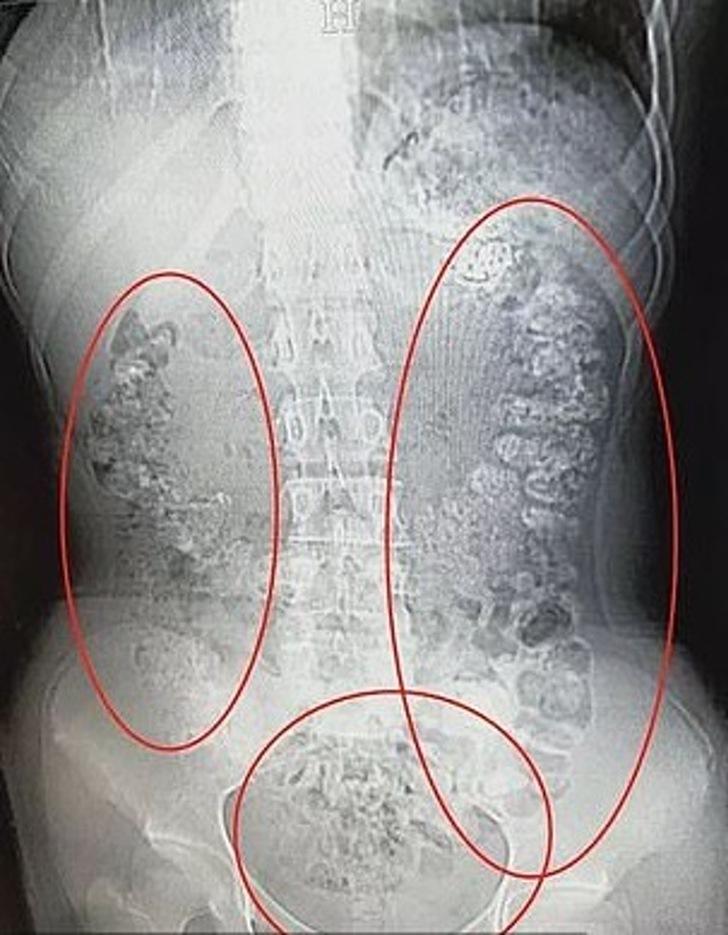

A fines de mayo, Xiao Shen despertó con fuertes dolores de estómago, por lo que sus padres la llevaron hasta el recinto médico más cercano donde se le realizó una serie de exámenes y radiografías.

Los resultados fueron impactantes. El doctor Zhang Louwei encontró más de 100 bolitas de tapioca en su sistema gástrico, esto por la gran cantidad de bubble tea que bebió en los días previos, según consignó Upsocl.

El profesional explicó que el almidón de la tapioca es muy difícil de digerir, por lo que las bolitas se fueron almacenando en su interior. Para la suerte de Xiao Shen, la solución era muy fácil: el doctor le recetó laxantes para ayudarla a soltar las pelotitas.